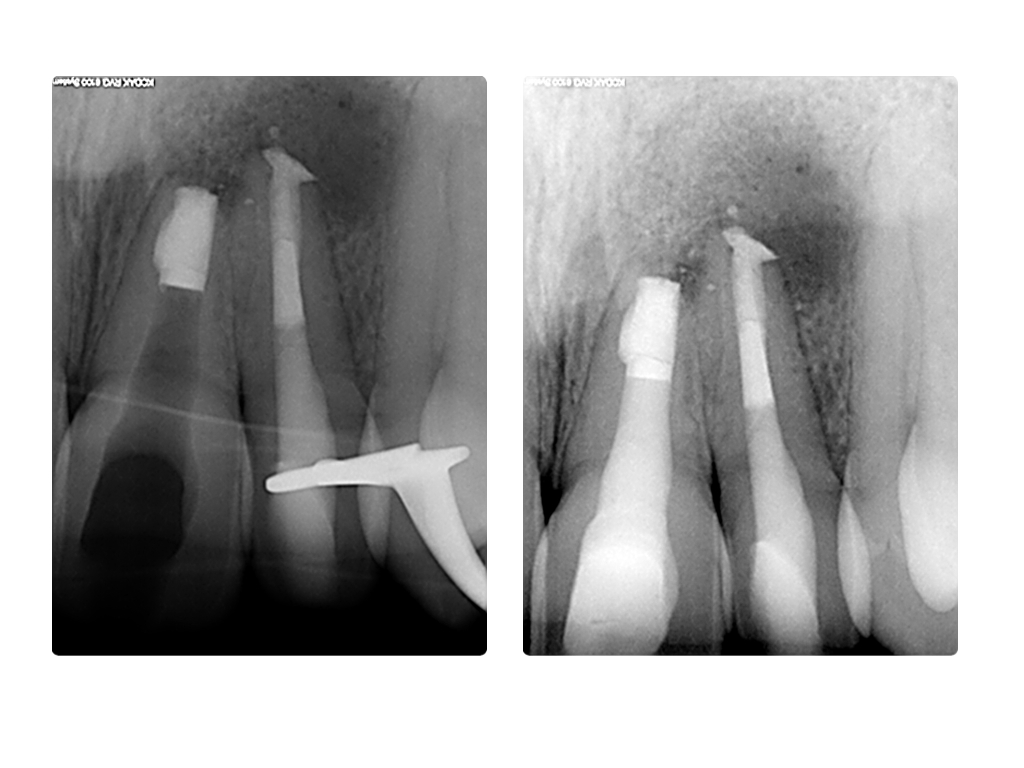

Einbahnstraße WSR (2)

WF 21 und 22